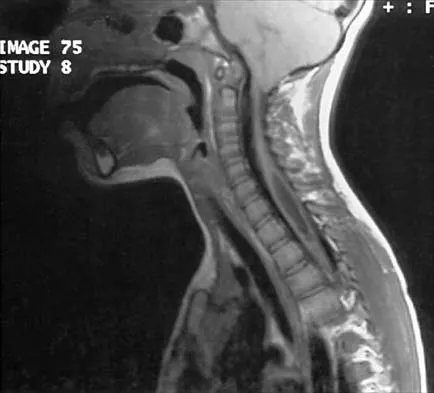

Question 23

A 42-year-old woman reports that she has low back pain and had a transient loss of consciousness after falling off a horse. She denies having neck pain but notes that she was involved in a motor vehicle accident 2 years ago and had neck pain at that time. Examination reveals full range of motion of the neck and no localized tenderness. The neurologic examination is normal. A lateral radiograph of the cervical spine is obtained. Figures 41a and 41b show CT and MRI scans. What is the most likely diagnosis?

Explanation

The examination findings do not correlate with an acute injury (full range of cervical motion and the absence of pain). Radiographically, the fracture appears old based on the smooth contour of the fracture fragments and the absence of soft-tissue swelling. Flexion-extension radiographs can be obtained to determine potential instability; if present, stabilization and fusion should be considered. Schatzker J, Rorabeck CH, Waddell JP: Non-union of the odontoid process: An experimental investigation. Clin Orthop 1975;108:127-137.